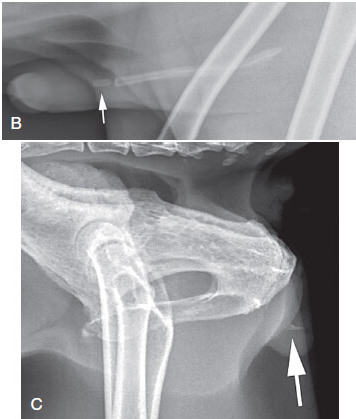

The os penis is sometimes mistaken for a urethral calculi when it has a?

Separate center of ossification - rare

What are urethrograms good at diagnosing?

Strictures (congenital, inflammatory, neoplasia)

Calculi